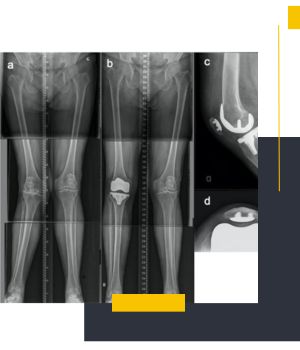

استفاده از دستگاههای دیجیتال نسل جدیدکیفیت بالای تصاویر و نمایش دقیق محور پا باعث میشود تشخیص و ارزیابی پزشکان با اطمینان بیشتری انجام شود.

تهیه عکس در حالت ایستاده برای بررسی واقعی محور اندام

عکسهای الایمنت ویو در مروارید ری طبق استانداردهای ارتوپدی و در وضعیت صحیح ایستاده گرفته میشود تا نتیجه کاملاً دقیق و قابل اعتماد باشد.

تیم مجرب مرکز با انجام روزانه تعداد زیادی از تصاویر اندام تحتانی مهارت بالایی در ثبت درست زاویهها و محورهای استخوانی دارد.